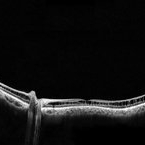

Retinoschisis

A 14-year-old male patient was admitted for visual assessment. Visual acuity without s / c in the right eye counts fingers and 20/80 in the left eye. According to family members, he reported low vision since childhood. He had previously been treated with photocoagulation at another service for which he had a diagnostic hypothesis of Coats' disease. Laboratory tests were requested (HIV, TOXO, TOXOCARIASIS, ECA, VDRL, PPD). In the evaluation, there was significant exudation in the posterior pole, some vascular irregularities in the right eye. In the left eye, there is a retinoschisis affecting the entire posterior pole and the nasal region to the optic disc, a macula with the characteristic aspect of a star. Well exemplified by OCT-A (Structure Deep: IPL - 25, OPL - 25).

Photographer: JEFFERSON R SOUSA - Study Center and Ophthalmological Research Dr. Andre M V Gomes, Institute Dr. Suel Abujamra São Paulo-Brazil

Imaging device: Optical Coherence Tomography system OCT CIRRUS 5000, Line Protocol, HD 21 line. Cirrus 5000 does not do a wide-angle tomographic image. This assembly was done manually with the junction of 11 lanes of 9mm each.

Condition/keywords: Coats' disease, retinoschisis